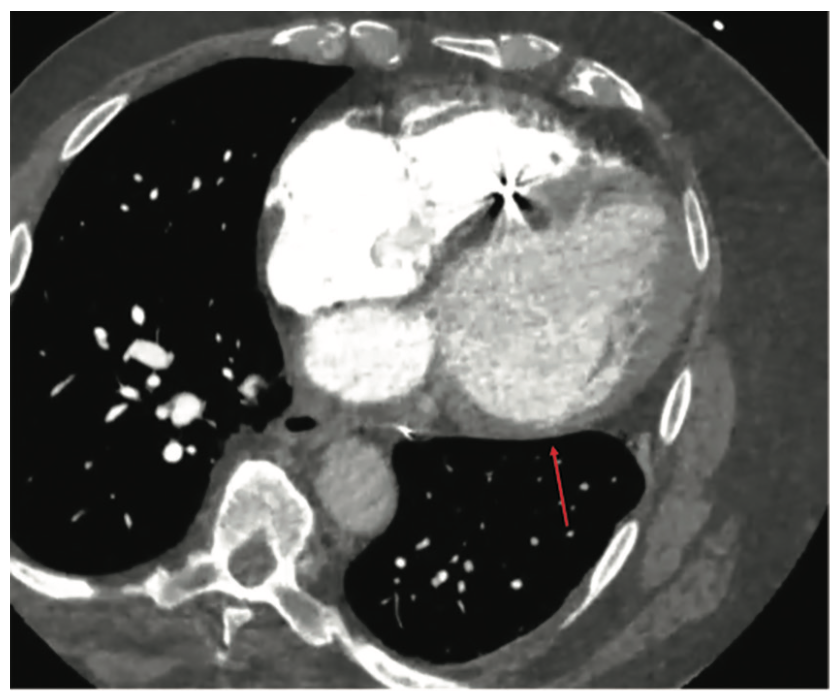

Preoperative workup of the patient included transthoracic echocardiography (TTE), computed tomography (CT), and magnetic resonance imaging (MRI). TTE confirmed the previously described severely reduced LVEF and did not show visible thrombus. Cardiac CT (Figure 1) revealed thinning of the basal LV wall segments, and cardiac MRI demonstrated late gadolinium enhancement (LGE) in the mid-myocardial and epicardial regions (Figure 2).

There is an established role for multimodality imaging in VT ablation. This is particularly true in NICM, as the underlying substrate is commonly more heterogeneous and complex in structure than in ischemic cardiomyopathy. Myocardial LGE on MRI can identify endocardial, mid-myocardial, epicardial, and transmural scars. Identification of the precise arrhythmogenic substrate can decrease procedural and ablation time, as well as increase efficacy in the long term.2 By excluding intracavitary thrombi either by MRI or CT, procedural safety can also be enhanced. Specifically for epicardial procedures, CT of the abdomen can depict the anatomy of the upper abdominal cavity, where injury to the liver or intestinal tract can occur.